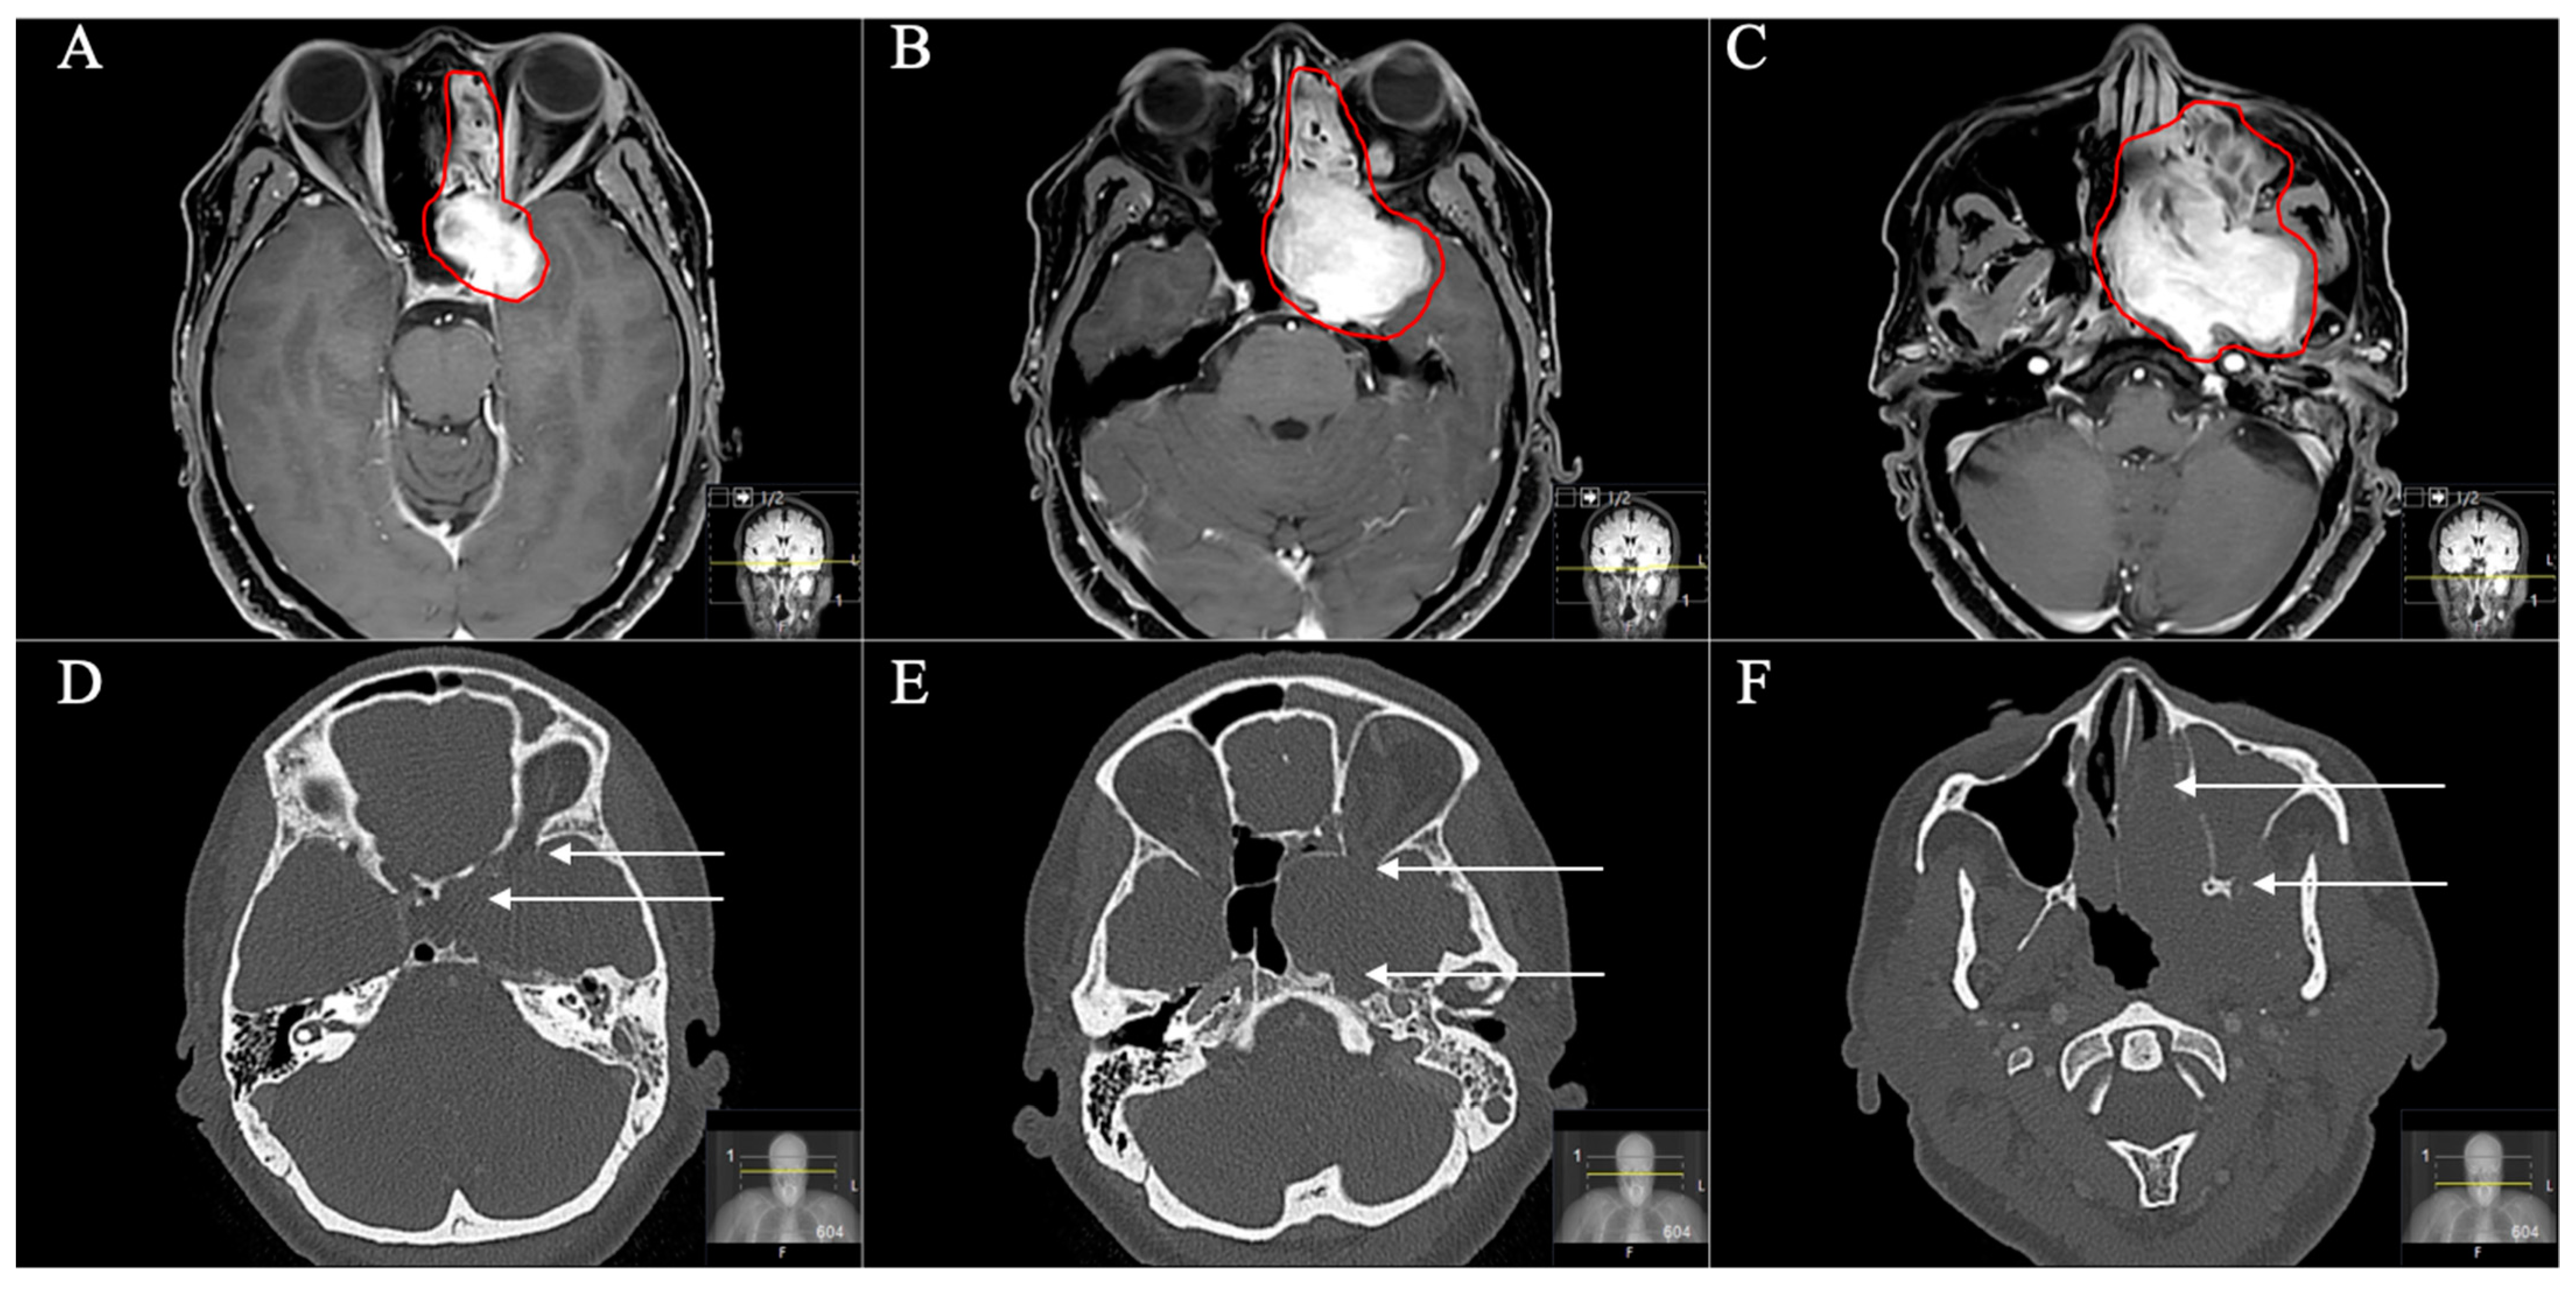

Figure 4. A 39-year-old male patient with neurofibromatosis type 2 presented with progressive vertigo, intermittent right facial pain and trigeminal hypesthesia (V1). (A) Preoperative axial and (B) coronal T1-weighted gadolinium-enhanced MRI, showing an impressive space-occupying cystic trigeminal schwannoma, involving the middle (MF) and posterior fossa (PF) through Meckel’s cave (Samii Type C). (C) Postoperative axial and (D) coronal MRI control, indicating complete resection via a two-stage technique; a modified Kawase and a retrosigmoid approach were performed. Postoperatively, no new deficits occurred and the patient recovered from the facial pain.